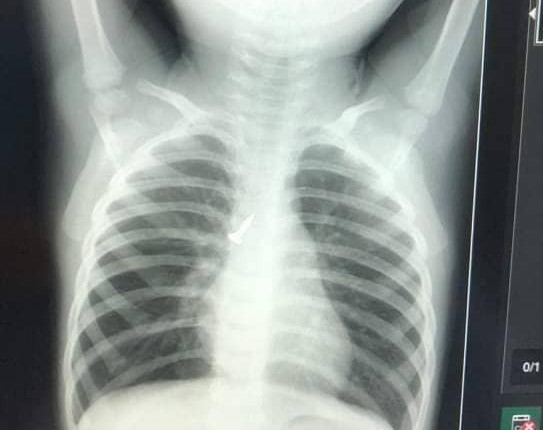

Theo đó, chiều 26/6, cháu D.T.V (17 tháng tuổi) trú tại xóm Thuận Phú, xã Thuận Sơn uống nước dừa và bị hóc cùi dừa.

Ngay khi phát hiện sự việc, gia đình lập tức đưa cháu bé đi cấp cứu tại Bệnh viện Đa khoa huyện Đô Lương. Dù đã được các y bác sĩ hết mình cứu chữa, cháu bé không qua khỏi.